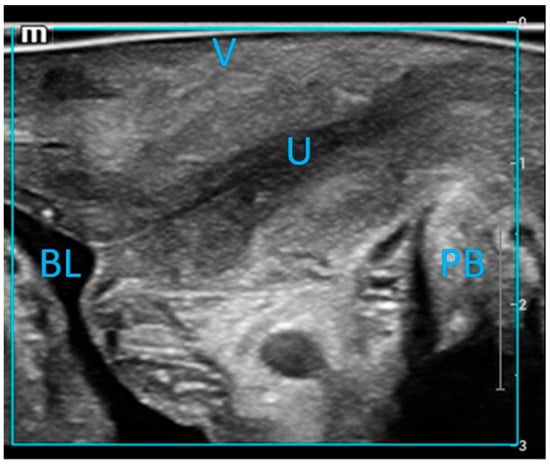

2.2. Ultrasound Examination